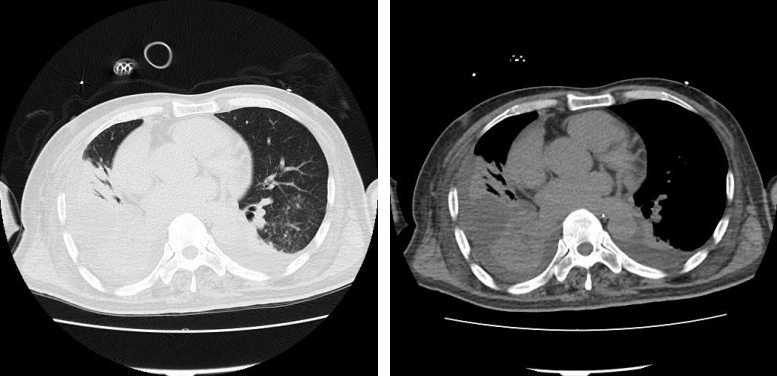

影像学

11月7日胸部CT:双肺炎性渗出,心包积液,双肺胸腔积液,右侧为著。

图片